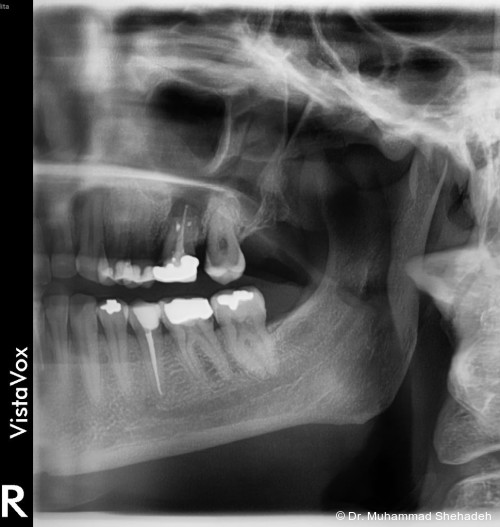

Im orthopantomografischen (OPG) Bild zeigte sich Zahn 26 wurzelbehandelt mit einer periapikalen osteolytischen Läsion. Etwa 15 mm kranial der apikalen Region des Zahns war eine röntgendichte Raumforderung in der linken Kiefer­höhle erkennbar. Die endodontische Versorgung des Zahns 26 erschien insuffizient. Der Zahn war klopfemp­findlich.

Radiologisch zeigte sich die retrograde Füllung im Rahmen der WSR regelrecht. Auffällig war, dass die ­beiden bukkalen Wurzeln nicht gefüllt waren; möglicherweise war die Füllung aufgrund der chronischen Entzündung resorbiert. Dem weiterbehandelnden Zahnarzt wurde daher eine Revision der Wurzel­kanal­behand­lung empfohlen.

Alternativ wäre bei erneuten Beschwerden eine Extraktion des Zahns 26 in Erwägung zu ziehen. Die Entscheidung, den Zahn initial zu erhalten, erfolgte bewusst, um die Heilung des Sinusbodens zu fördern und das Risiko einer großflächigen oroantralen Verbindung zu minimieren. Somit bleibt perspektivisch die Möglichkeit einer späteren Implantatversorgung erhalten.